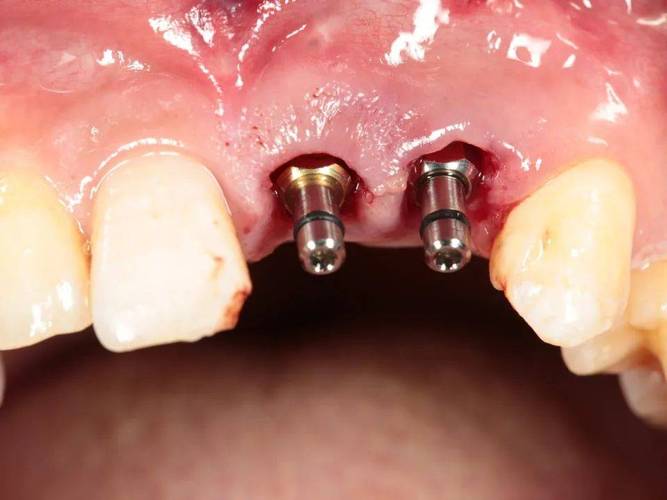

(三)种植体植入

- 种植体选择:优先选择表面粗糙化(如喷砂酸蚀、SLA表面)的种植体,促进骨结合;直径根据骨量选择(前牙区3.5-4.5mm,后牙区4.5-5.5mm),长度≥8mm(确保植入后种植体尖端超过牙槽窝底1-2mm,避免损伤重要神经血管)。

- 植入方向与深度:种植体长轴与邻牙牙根平行,避免偏向邻牙导致邻牙损伤;植入深度应使种植体平台位于牙槽嵴顶下方0.5-1mm(为牙龈愈合提供空间,避免平台暴露)。

- 初期稳定性确认:植入后用扭矩扳手测量植入扭矩,若<35N·cm,可调整种植体位置(如加深植入深度或改变角度),或选择直径稍小的种植体;若仍无法达到,则放弃即刻种植,改为延期种植。